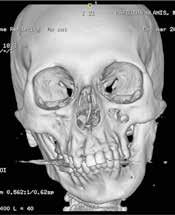

Para completar el estudio, se solicitó una tomografía axial computoriza da craneofacial (TAC) (Figura 1), dónde tras un examen exhaustivo a través de distintos cortes y reconstrucción 3D, evidenciamos una anquilosis de la ATM a la base de cráneo, desapareciendo por completo la anatomía nor mal de la ATM y su relación habitual con las distintas estructuras neurovas culares, así como la gran deformidad esquelética resultante del crecimiento y desarrollo craneofacial anormal.

Gracias a esta planificación, se logró una mayor precisión en los movi mientos quirúrgicos, una mayor predictibilidad y reproducción, una dismi nución de los riesgos quirúrgicos por mediciones de estructuras anatómicas concretas (como la arteria carótida interna, el nervio facial, el nervio man dibular, la arteria maxilar interna…) (Figura 1) y un menor tiempo operato rio, entre otras ventajas.

Figura 1. Diagnóstico prequirúrgico del bloque anquilótico. Imágenes TAC en 3D, corte axial y corte sagital..